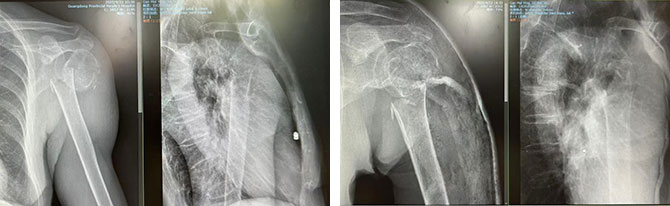

患者2:女,85岁,外科颈骨折

复位前 复位后